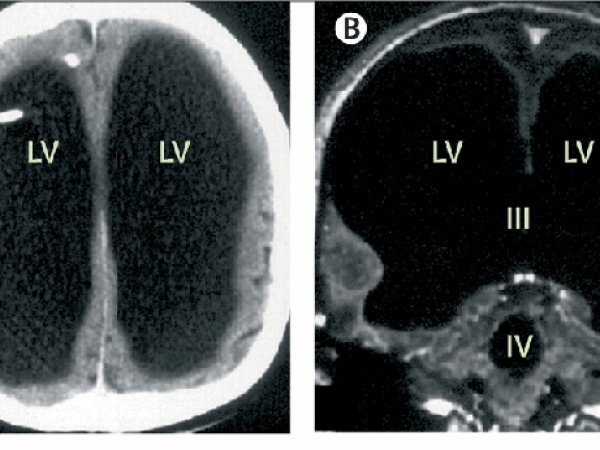

Огляд і перше дослідження ніг результатів не дали, тому доктор послав пацієнта пройти повне обстеження. І коли черга дійшла до голови, медична допомога вже знадобилася самим лікарям: тому що сканування показало, що у чоловіка настільки маленький мозок, що його спочатку фахівці навіть не розгледіли.

Пізніше з'ясувалося, що такий феномен виник через те, що вся спинномозкова рідина, яка в нормі циркулює по мозку і виводиться в кровоносну систему, заповнила майже весь череп, залишивши лише невелику частину сірої речовини.

Звідки така кількість рідини? Виявляється, в дитинстві чоловіка лікували від гідроцефалії, так називаються випадки, коли в головному мозку накопичується зайва рідина. Тоді лікування пройшло успішно, і через час чоловік повністю забув про свою дитячу проблему.